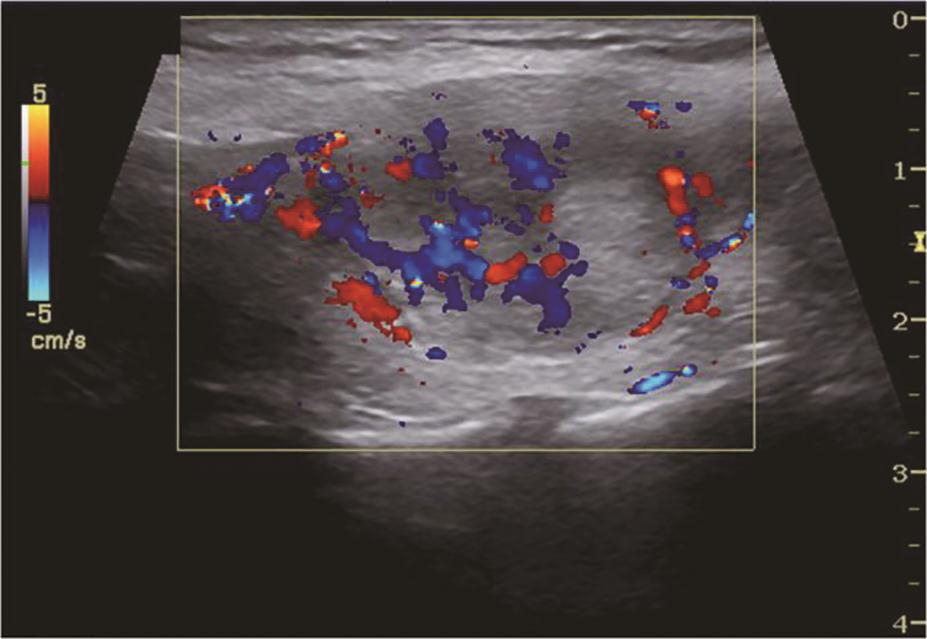

甲状腺滤泡癌和滤泡腺瘤在超声上鉴别有一定困难,即使是FNA细胞学也很难鉴别。但有报道认为:与甲状腺乳头状癌不同,甲状腺滤泡癌常为等回声或高回声,微小钙化很少见,病变多伴有厚薄不一的低回声晕或者局部低回声晕。彩色多普勒血流信号丰富也是该类病变的特点之一(图11、图12)。

图12右侧颈部纵切面(与图3-3-11同患者、同切面):中等回声彩色多普勒血流信号丰富而杂乱